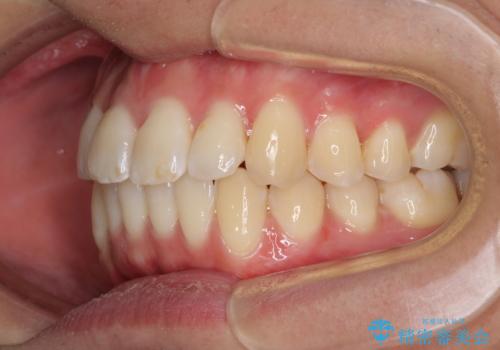

- 前歯のデコボコと若干口元が突出していることを気にして来院された患者様です。

全体的に軽微な叢生が認められ、口元もやや前方に突出していたため、インビザラインでのIPR(歯と歯の間を削る)と歯列全体の後方移動によって歯並びを整えることとしました。

上下ともに歯列の幅が狭かったため、側方に拡大することで前歯のデコボコや突出感を解消するためのスペースを獲得することができました。

歯並びが改善したことはもちろん、咬み合わせの改善まで実感することができ、患者様には大変満足していただけました。